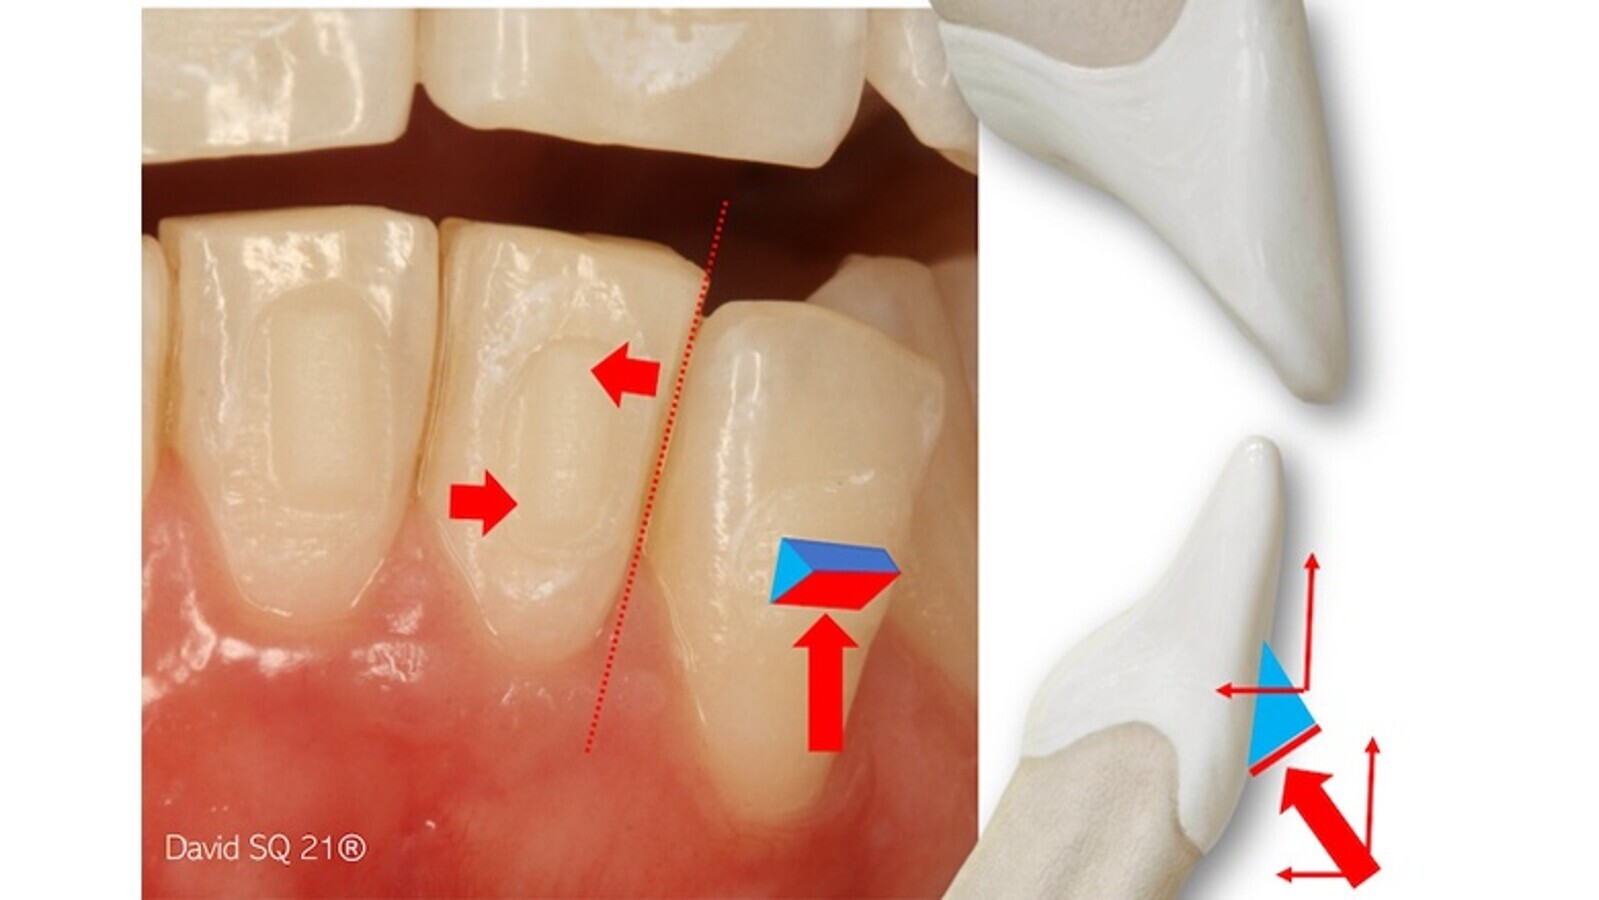

En el movimiento de torsión radicular positiva, hacia palatino, también apreciamos diferencias biomecánicas significativas entre el uso de brackets o alineadores (figura 3). Como es de todos conocido, en el primer caso recurrimos al par de fuerzas generado por el arco rectangular dentro de la ranura o slot, haciendo que la tracción distal del arco (ligado en distal) anule en parte el vector de vestibulización y genere un desplazamiento del centro de rotación hacia el borde incisal, siendo máximo el movimiento apical. En el caso de los alineadores contamos con la inestimable ayuda envolvente del plástico, lo que nos permite ejercer una fuerza desde vestibular (prominencia o arco de torque vestibular) y otra desde lingual (punto de presión cercano al borde incisal), desplazando hacia incisal el centro de rotación y maximizando el movimiento apical (figura 3).

Figura 3. El movimiento de torsión radicular positiva, hacia palatino, muestra diferencias biomecánicas significativas entre el uso de brackets o alineadores.